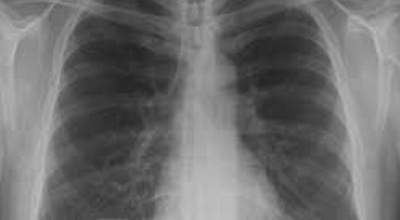

일반인이 근육의 통증과 금이 간 경우의 차이는 거의 판별하기 힘들게 됩니다. 갈비뼈라고 하는 부분이 눈에 보이도록 붓는 것도 아니고, 멍이 들어서 아픈것도 아니기 때문이예요. 가장 정확하게 판별하는 방법은 엑스레이를 찍는 방법이예요.